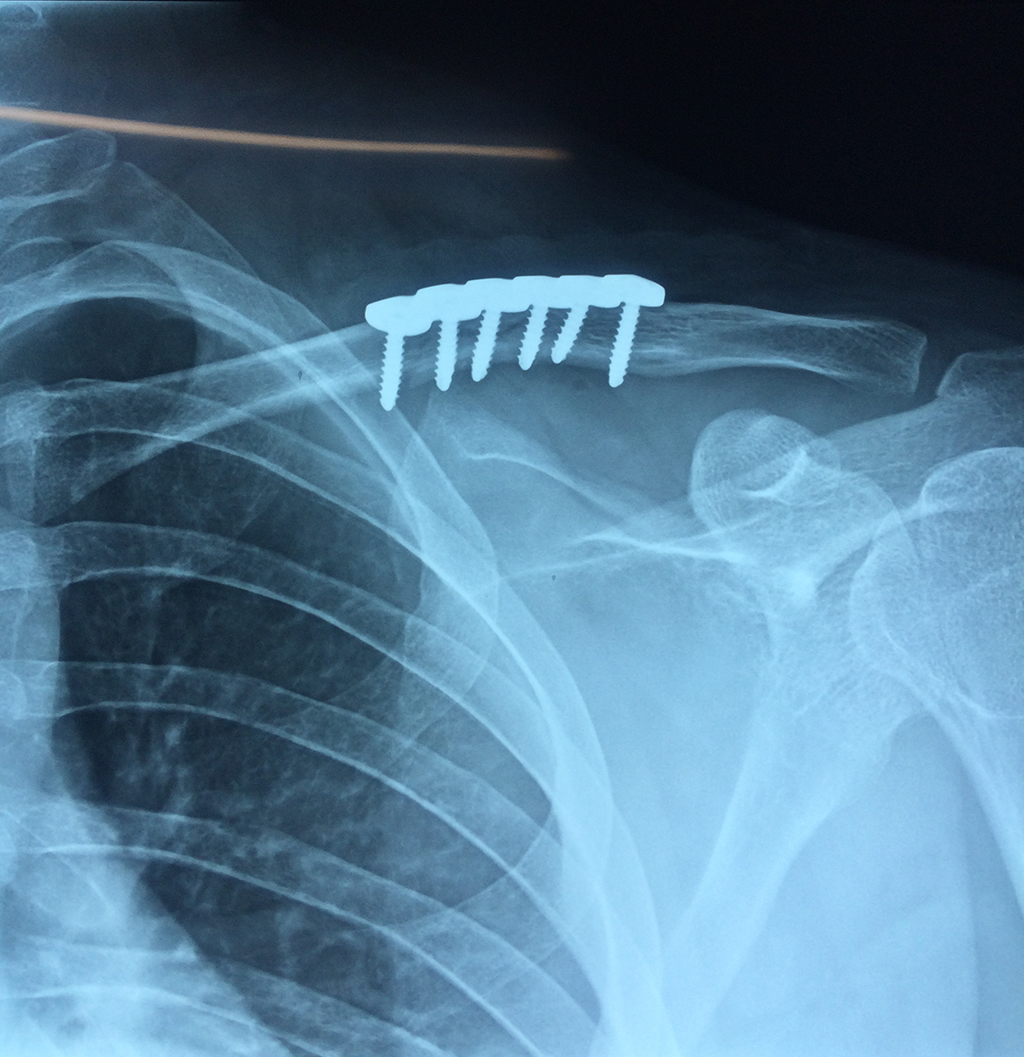

Cirugías de Calcaneo - Clavícula

La clavícula es un hueso largo, con forma de "S" itálica, situado en la parte anterosuperior del tórax. Junto con la escápula forman la cintura escapular. Se puede palpar por toda su longitud y se extiende del esternón al acromion de la escápula, siguiendo una dirección oblicua lateral y posterior.